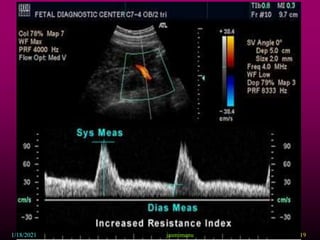

This document provides information about intrauterine growth restriction (IUGR), including its definition, classification, etiology, diagnosis, treatment and risks. IUGR occurs when a baby's growth is slowed or restricted during pregnancy. It can be symmetric, affecting overall growth, or asymmetric, affecting the growth of some parts more than others. The causes of IUGR are often unknown but can include maternal, fetal, placental or genetic factors. Diagnosis involves assessing growth via ultrasound and monitoring blood flow. Treatment may involve bed rest, aspirin or early delivery depending on gestational age and fetal wellbeing. Both short and long term risks to the infant are increased with IUGR.